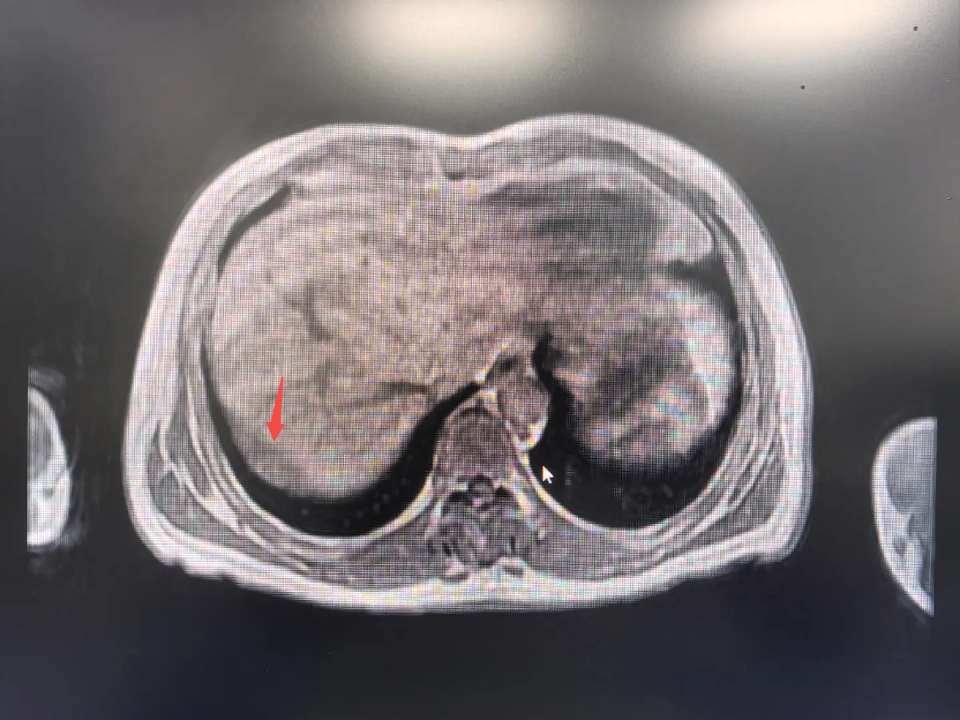

患者李爷爷(化名)有着多年的结肠癌病史,近期体检中发现肿瘤标志物升高,PET/CT检查提示右膈下腹膜出现新发病灶。这个位置极为特殊——膈肌是分隔胸腹腔的“生命穹顶”,肿瘤紧贴其上,如同在“天花板”上埋下隐患。

在分离过程中,团队不仅找到了约5cm*4cm的预定目标病灶,还意外发现了肝脏上一个0.5cm的微小病灶。经现场评估,决定将这两个“炸弹”一并拆除。

最关键的步骤是切除紧贴膈肌的大肿瘤。主刀医生在距离肿物边缘1cm处精细操作,逐步将其从膈肌上剥离。正如术前所料,肿瘤已与膈肌紧密粘连。胸外科医生立即上台协助,两位专家联手,果断切除受侵犯的膈肌部分,随即在腹腔镜下展开精细修补。在严重受限的空间内缝合穹顶状的膈肌,其难度堪比“在碗底穿针引线”。每一针都考验着医生的手上功力与专注力。缝合完成后,麻醉医生进行鼓肺测试,确认修补严密无泄漏。